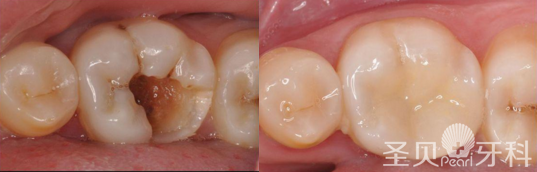

牙齿烂了怎么办?一般来说,牙齿烂了是龋齿的表现,它是以牙体被腐蚀,逐渐毁坏而成龋洞的牙病,可分为浅龋、中龋、深龋。

圣贝指出:未经治疗的龋洞是不会自行愈合的,其发展的最终结果是牙齿丧失,所以牙齿烂了一定要及时到医院检查,由判定龋坏程度,采取相应的治疗方法。>>>一对一挂号治疗方案

1.浅龋:龋坏仅局限于牙齿表面,此时患者常无自觉症状,一般在牙医检查时可看到牙齿窝沟或牙面有白色粉笔样斑,或是色素沉着形成墨浸状斑,治疗浅龋充填的效果最好。

2.中龋或深龋:龋蚀侵及牙本质深层,有明显龋洞,对冷热酸甜刺激敏感。在去净龋坏组织以后,有时洞底已接近牙髓,就需要在洞底加一层护髓剂再填初。有时深龋在去净龋坏组织以后牙髓就暴露了,就需要先采取牙髓治疗,然后才能填充。

同时,圣贝引进高精技术和设备,结合3M纳米树脂材料补牙,它相对传统复合树脂类材料,具有性能更高、色泽更好、更耐磨且不易脱落等多重优势,满足患者高要求、多样的个性需求。